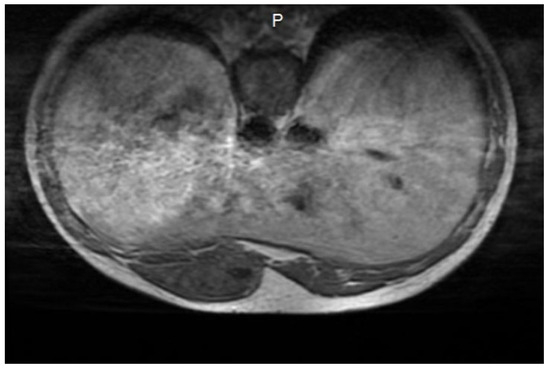

The Incidence of Oncocytoma and Angiomyolipoma in Patients Undergoing Nephron-Sparing Surgery for Small Renal Masses

Stelian Ianiotescu, Constantin Gingu, Irina Balescu, Nicolae Bacalbasa, Cristian Balalau and Ioanel Sinescu

Background: Oncocytoma and angiomyolipoma (AML) are benign renal tumors that may mimic malignant lesions on imaging. With the increasing use of partial nephrectomy (PN) for renal masses, accurate preoperative characterization of these lesions is essential. This study highlights the role of partial nephrectomy

Background: Oncocytoma and angiomyolipoma (AML) are benign renal tumors that may mimic malignant lesions on imaging. With the increasing use of partial nephrectomy (PN) for renal masses, accurate preoperative characterization of these lesions is essential. This study highlights the role of partial nephrectomy as a valuable diagnostic tool in situations where imaging is inconclusive or raises concern for malignancy without definitive confirmation. In the absence of a reliable preoperative diagnosis, partial nephrectomy provides direct histologic verification with minimal perioperative morbidity. Moreover, it offers curative potential when malignancy is present. By achieving both diagnostic certainty and renal preservation, this approach is well-suited for clinical scenarios in which imaging ambiguity might otherwise result in overtreatment through radical surgery or undertreatment Material and methods: in this retrospective study, we reviewed our 5-year experience (2019–2024), 188 partial nephrectomies—including bilateral procedures and operations on solitary kidneys—using robotic and open approaches. All of these 30 tumors were solid renal masses with indeterminate imaging features or suspicious characteristics suggestive of malignancy, further underscoring the limitations of current preoperative diagnostic modalities. Results: Histopathological evaluation confirmed benign renal tumors in 30 cases, with oncocytoma diagnosed in 18 cases (16 robotic, 2 open) and AML in 12 cases (9 robotic, 3 open). Conclusions: Even when imaging raises suspicion of malignancy or remains inconclusive, many small renal masses are ultimately confirmed as benign upon histopathological examination. This study underscores the diagnostic uncertainty associated with small renal tumors and highlights the value of partial nephrectomy as a decisive diagnostic intervention. In situations where non-invasive modalities fail to provide definitive answers, partial nephrectomy offers tissue confirmation with minimal morbidity. Furthermore, when malignancy is present, this approach ensures appropriate oncologic management while preserving renal function. Our findings support the integration of this strategy into routine clinical practice, particularly when diagnostic clarity is essential for guiding safe and effective treatment.